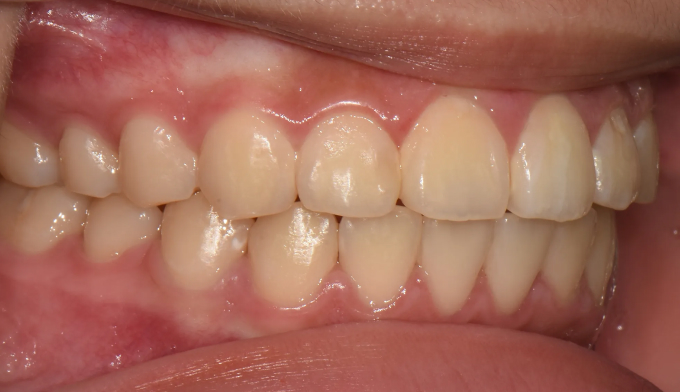

After